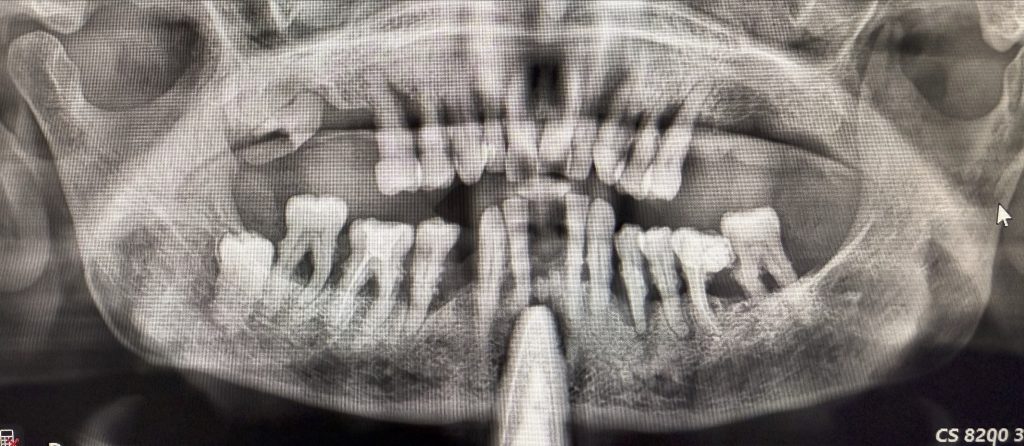

Il paziente si è presentato alla nostra attenzione a causa di un grave inestetismo e discomfort legato a una protesi parziale rimovibile superiore incongrua eseguita in seguito ad estrazioni multiple superiori e inferiori per parodontopatia avanzata mai curata in precedenza.

In anamnesi non sono state segnalate controindicazioni a interventi chirurgici (Figure 1-2).